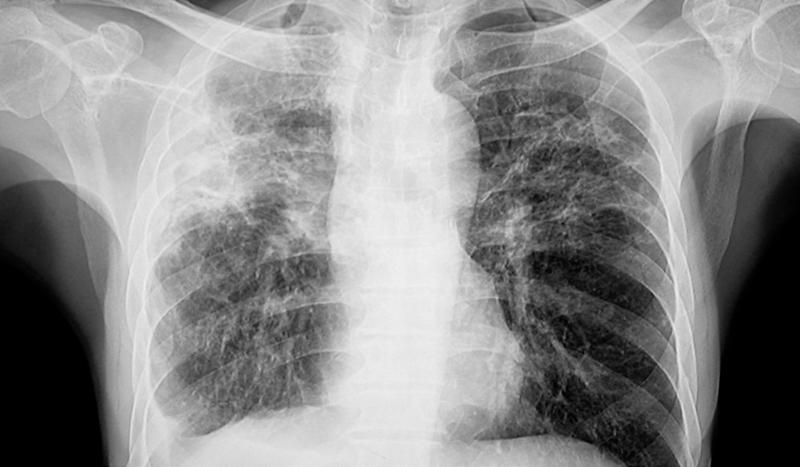

A new centre for tuberculosis care

It’s a common misconception that tuberculosis (TB) is a disease of the past - over 1.25 million people across the world died of TB in 2023 alone.

Right now, East London has one of the highest rates of newly diagnosed cases in Western Europe. And the average age of a TB patient seen at Barts Health is just 30-35 years old.

Delays in diagnosis can cause lifelong issues for patients and have devastating physical effects that can also impact mental wellbeing. A number of patients in East London die of TB each year, despite the world class treatment available.

That’s why, with the help of our supporters, we’ve committed to fund the new Queen Mary and Barts Health Tuberculosis Centre.

Teams of researchers, clinical experts and TB advocates will work together to deliver improvements in how we understand, diagnose, treat and campaign for TB care, helping patients not just in our local community but around the world.

Amy is a TB survivor and advocate, who’ll be working with experts at the Centre. She knows first-hand just how important this support will be for other TB patients, after developing TB when she was at university. Amy had to have her left lung removed and will experience the effects for the rest of her life. “TB is quite a lonely disease,” she says.